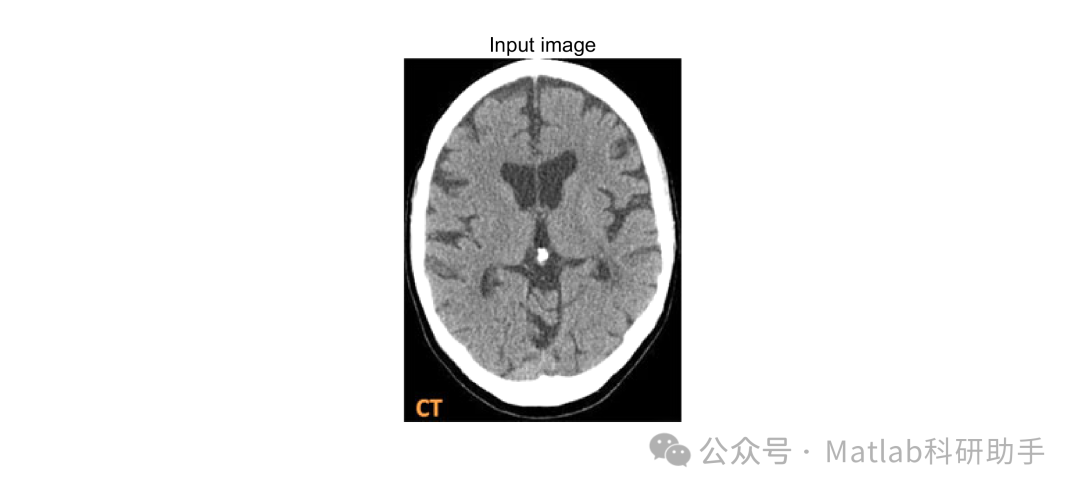

⛳️ 运行结果

将各向异性滤波器应用于 MRI 图像,能够有效去除噪声,同时保持脑肿瘤和正常组织的边缘 。在去除噪声方面,它可以平滑图像中因成像设备或环境因素产生的随机噪声,使图像更加清晰 。对于脑肿瘤区域,由于肿瘤边界处的梯度较大,各向异性滤波器能够避免过度平滑,保留肿瘤的边缘信息,为后续的肿瘤分割和特征提取提供更好的图像基础 。例如,在 T2 加权像中,经过各向异性滤波处理后,肿瘤组织与周围水肿区域的边界更加清晰,有利于准确区分肿瘤和正常组织 。